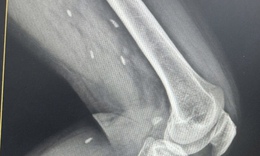

Cứu sống ngoạn mục cô gái 18 tuổi bị đa chấn thương do tai nạn giao thông

Y tế - 10/10/2025 16:23SKĐS - Sau tai nạn giao thông kinh hoàng, nữ sinh 18 tuổi được đưa vào Bệnh viện Đà Nẵng trong tình trạng nguy kịch, đa chấn thương, mất máu nhiều. Cuộc “chạy đua với tử thần” bắt đầu, các bác sĩ kích hoạt báo động đỏ, giành giật từng phút để giữ lại sự sống mong manh cho em.